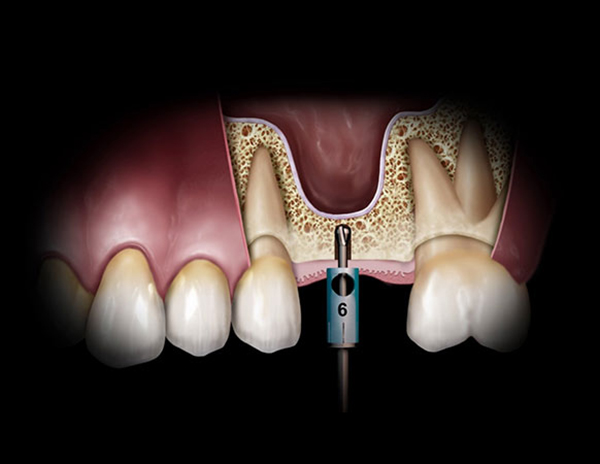

상악동이 위치한 위턱 부위에 임플란트를 식립하려 할 때 그 부위 뼈가 부족할 경우, 상악동과 임플란트 식립 부위 사이에 더 많은 뼈의 공간을 확보하기 위해서 시행하게 됩니다.

위에 그림을 보시면 노란색으로 보이는 부분이 뼈로 채워진 공간이며, 위에 비어 있는 공간이 상악동이라고 불리우는 곳인데요. 그림에서 보시다시피 임플란트가 들어가기에는 뼈의 공간이 충분하지 않은 것을 확인할 수 있습니다.

이런 경우 무리하게 임플란트 수술을 하게 되면 상악동이 천공되어 코와 입이 바람이 통하는 느낌이 나고, 코피가 계속 나거나 입에서 코로 물이 넘어가는 증상 등의 부작용이 생길 수 있기 때문에 밑으로 내려와있는 상악동 공간을 위로 올려주는 "상악동 거상술"이 필요하게 됩니다.

상악동을 덮고 있는 얇은 막을 위로 들어올려서 인공뼈로 채워 임플란트를 심을 수 있는 뼈를 확보한 이후 임플란트를 심게 됩니

다. 이와 같이 위턱 어금니 부위에 임플란트 수술과 병행하여 상악동 거상술을 시행하게 됩니다. 이는 임플란트와 잇몸뼈의 결합을 더 단단하게 하여 임플란트의 수명을 늘리기 위해 하는 수술이라 할 수 있습니다.